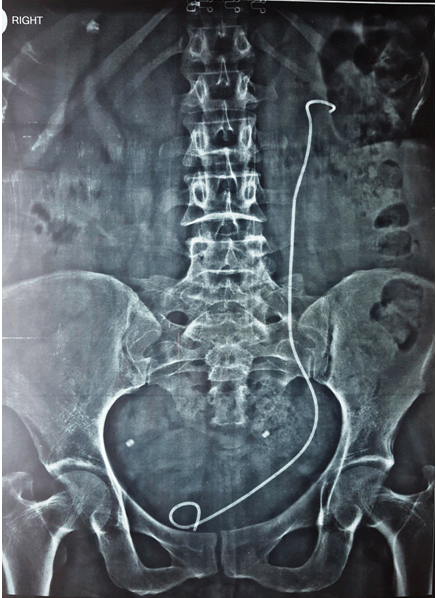

Ultrasound kidney, ureter, and bladder of the patient revealed essentially right sided normal kidney, while in left kidney there was a staghorn calculus of size about 25 mm, besides it there was a large bladder stone of size about 49 mm. Digital X-ray kidney, ureter, and bladder showed coiled ends of a double-J stent in the left renal pelvis and bladder region with formation of stones over it however entire shaft of the stent was missing (Figure 1). Her KFT was within the normal limit.

Figure 1: Digital X-ray kidney, ureter, and bladder of the patient showing A large bladder stone and a large staghorn calculus (in left renal pelvis) formed over J ends of double-J stent while central shaft has been disappeared due to stenturia.